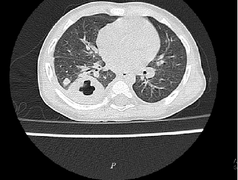

Bệnh cảnh lâm sàng của bệnh Whitmore đa dạng, phức tạp như sốt cơn hoặc sốt kèm theo lạnh run, sốt kéo dài, suy hô hấp, loét da, viêm đường tiết niệu, viêm phổi, áp xe phổi, áp xe ở gan, lách, nhiễm trùng huyết, suy đa phủ tạng, thường chẩn đoán nhầm với bệnh khác như viêm phổi, lao phổi, áp xe cơ…